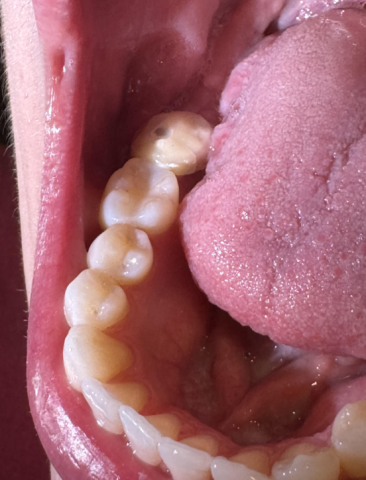

Image Observations: The picture shows the lower right side of the mouth (Mandibular quadrant).

The tooth farthest back (most posterior) appears to have a restoration (filling or inlay/onlay) or possibly a crown which exhibits a large, dark, and deep-looking defect or void on its biting surface (occlusal surface). The defect appears dark brown/black with a distinct border.

The adjacent tooth (second molar/premolar) also shows signs of an existing white or tooth-colored filling (composite or glass ionomer) with some possible discoloration or breakdown at the margins.

The surrounding soft tissues (gums and tongue) appear generally healthy.

Client Statement: "Does my crown implant look normal?"

Clarification: It is most likely that the question refers to a crown placed on a natural tooth, or a restoration on a natural tooth. A dental implant would typically have a crown cemented on an abutment, and the visible issue appears to be within the structure of the tooth/crown itself.

The primary concern is the large, dark defect on the most posterior tooth.